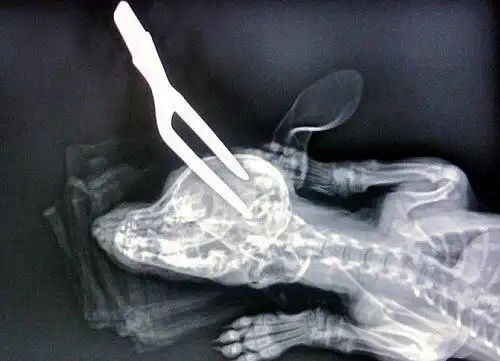

Неизвестно точно, что произошло с этой собачкой. говорят, она прыгнула на какой-то шкаф или комод с посудой. Но ей не повезло. Одна вилка каким-то непонятным образом упала на сабаку и воткнулась ей прямо в голову... Но лично я думаю, что животное кто-то пытался убить таким вот варварским методом...

К счастью, мозг животного и жизненно важные органы в голове не были задеты. Собачка оказалась крепким орешком. И после одной операции вилка была извлечена, а на голове остася шрам, который, надеемся, тоже когда-то заживет.